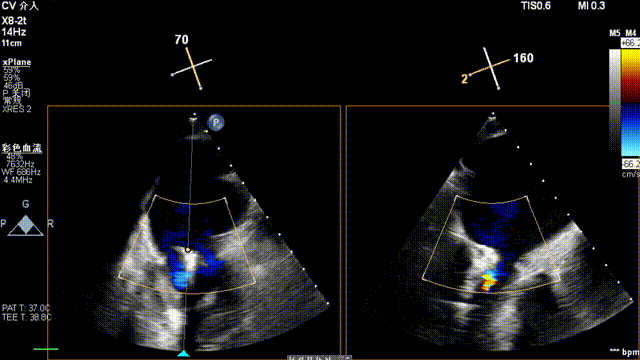

术中超声(关键步骤)

全麻后,二尖瓣夹合器系统在心前区的肋间切开3-4CM小切口,暴露心脏的心尖位置,送系统送入左心房,顺利到达病变二尖瓣区域。在经食道超声辅助下,术者通过反复评估二尖瓣反流位置、抓捕位置、反流程度,首先在2偏3区位置处于二尖瓣闭合线垂直进行巧妙夹合。在2区靠近3区位置处植入了1枚ValveClamp®MVC-IIf夹,最终评估评估反流降至轻度,平均跨瓣压差降至2mmHg,手术取得圆满成功。

最终在A3P2位置夹合,前叶夹合量10mm,后叶夹合量8mm,剩余瓣口面积3.45cm²,平均跨瓣压差2mmHg,反流基本消除。